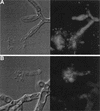

Caspofungin acetate is an antifungal antibiotic that inhibits synthesis of 1,3-beta-D-glucan, an essential component of the fungal cell wall. While caspofungin causes cell death in yeasts and dimorphic fungi such as Candida albicans, its effect on Aspergillus fumigatus is less well understood. We used the fluorescent dyes 5,(6)-carboxyfluorescein diacetate (CFDA) and bis-(1,3-dibutylbarbituric acid) trimethine oxonol (DiBAC), which stain live and dead cells, respectively, to further characterize the antifungal activity of caspofungin. For comparison, compounds whose mode of action was either fungistatic (fluconazole, itraconazole) or fungicidal (amphotericin B) were also evaluated. A correlation between caspofungin-induced loss of viability, decreased CFDA staining, and increased DiBAC staining was established first with C. albicans. For A. fumigatus, caspofungin caused similar dye-staining changes, which were quantified by fluorimetric analysis of stained hyphae grown in a medium that promoted dispersed growth. The minimum concentration of caspofungin required to produce these changes also decreased the level of growth-dependent reduction of the indicator dye Alamar Blue. We observed a differential effect of caspofungin as a function of cell position: 88% of apical cells and 61% of subapical branching cells failed to stain with the viable dye CFDA, but only 24% of subapical cells were unstained. Complementary results were seen with germlings from DiBAC-stained, caspofungin-treated cultures. Extended incubation of A. fumigatus with a single dose of caspofungin affected the same proportion of apical and subapical branching cells for up to 72 h. The dye-staining patterns illustrate that the cells at the active centers for new cell wall synthesis within A. fumigatus hyphae are killed when they are exposed to caspofungin.